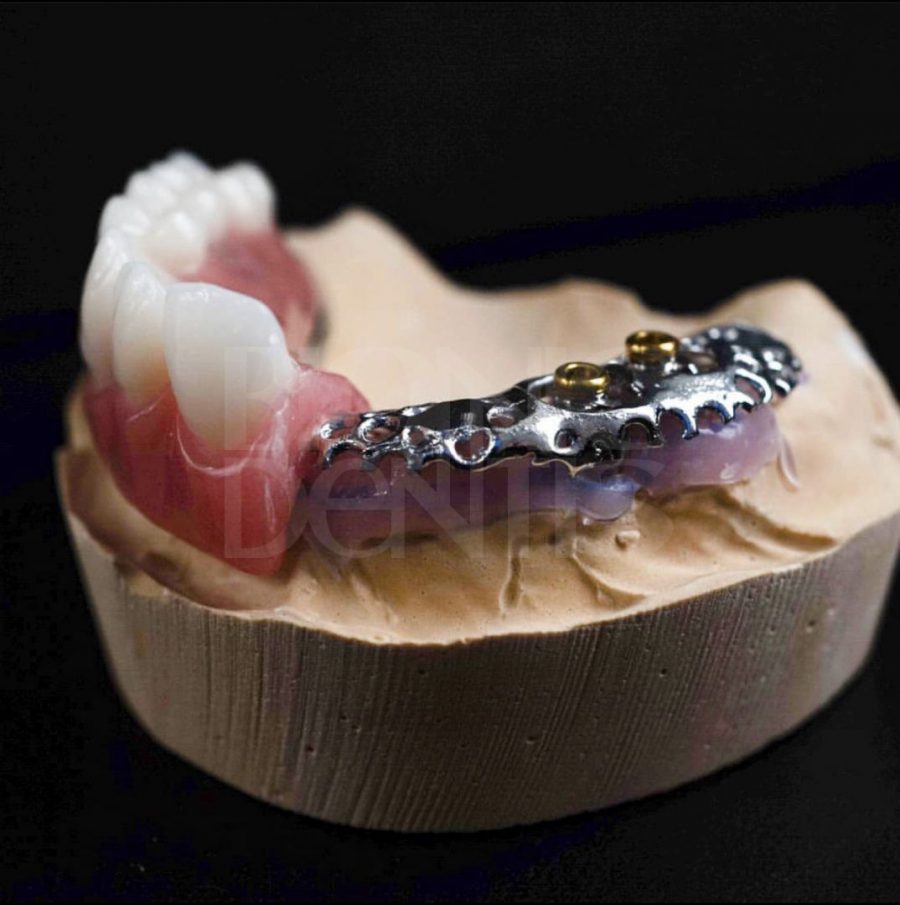

Современные съемные протезы на локаторах: Фото и примеры